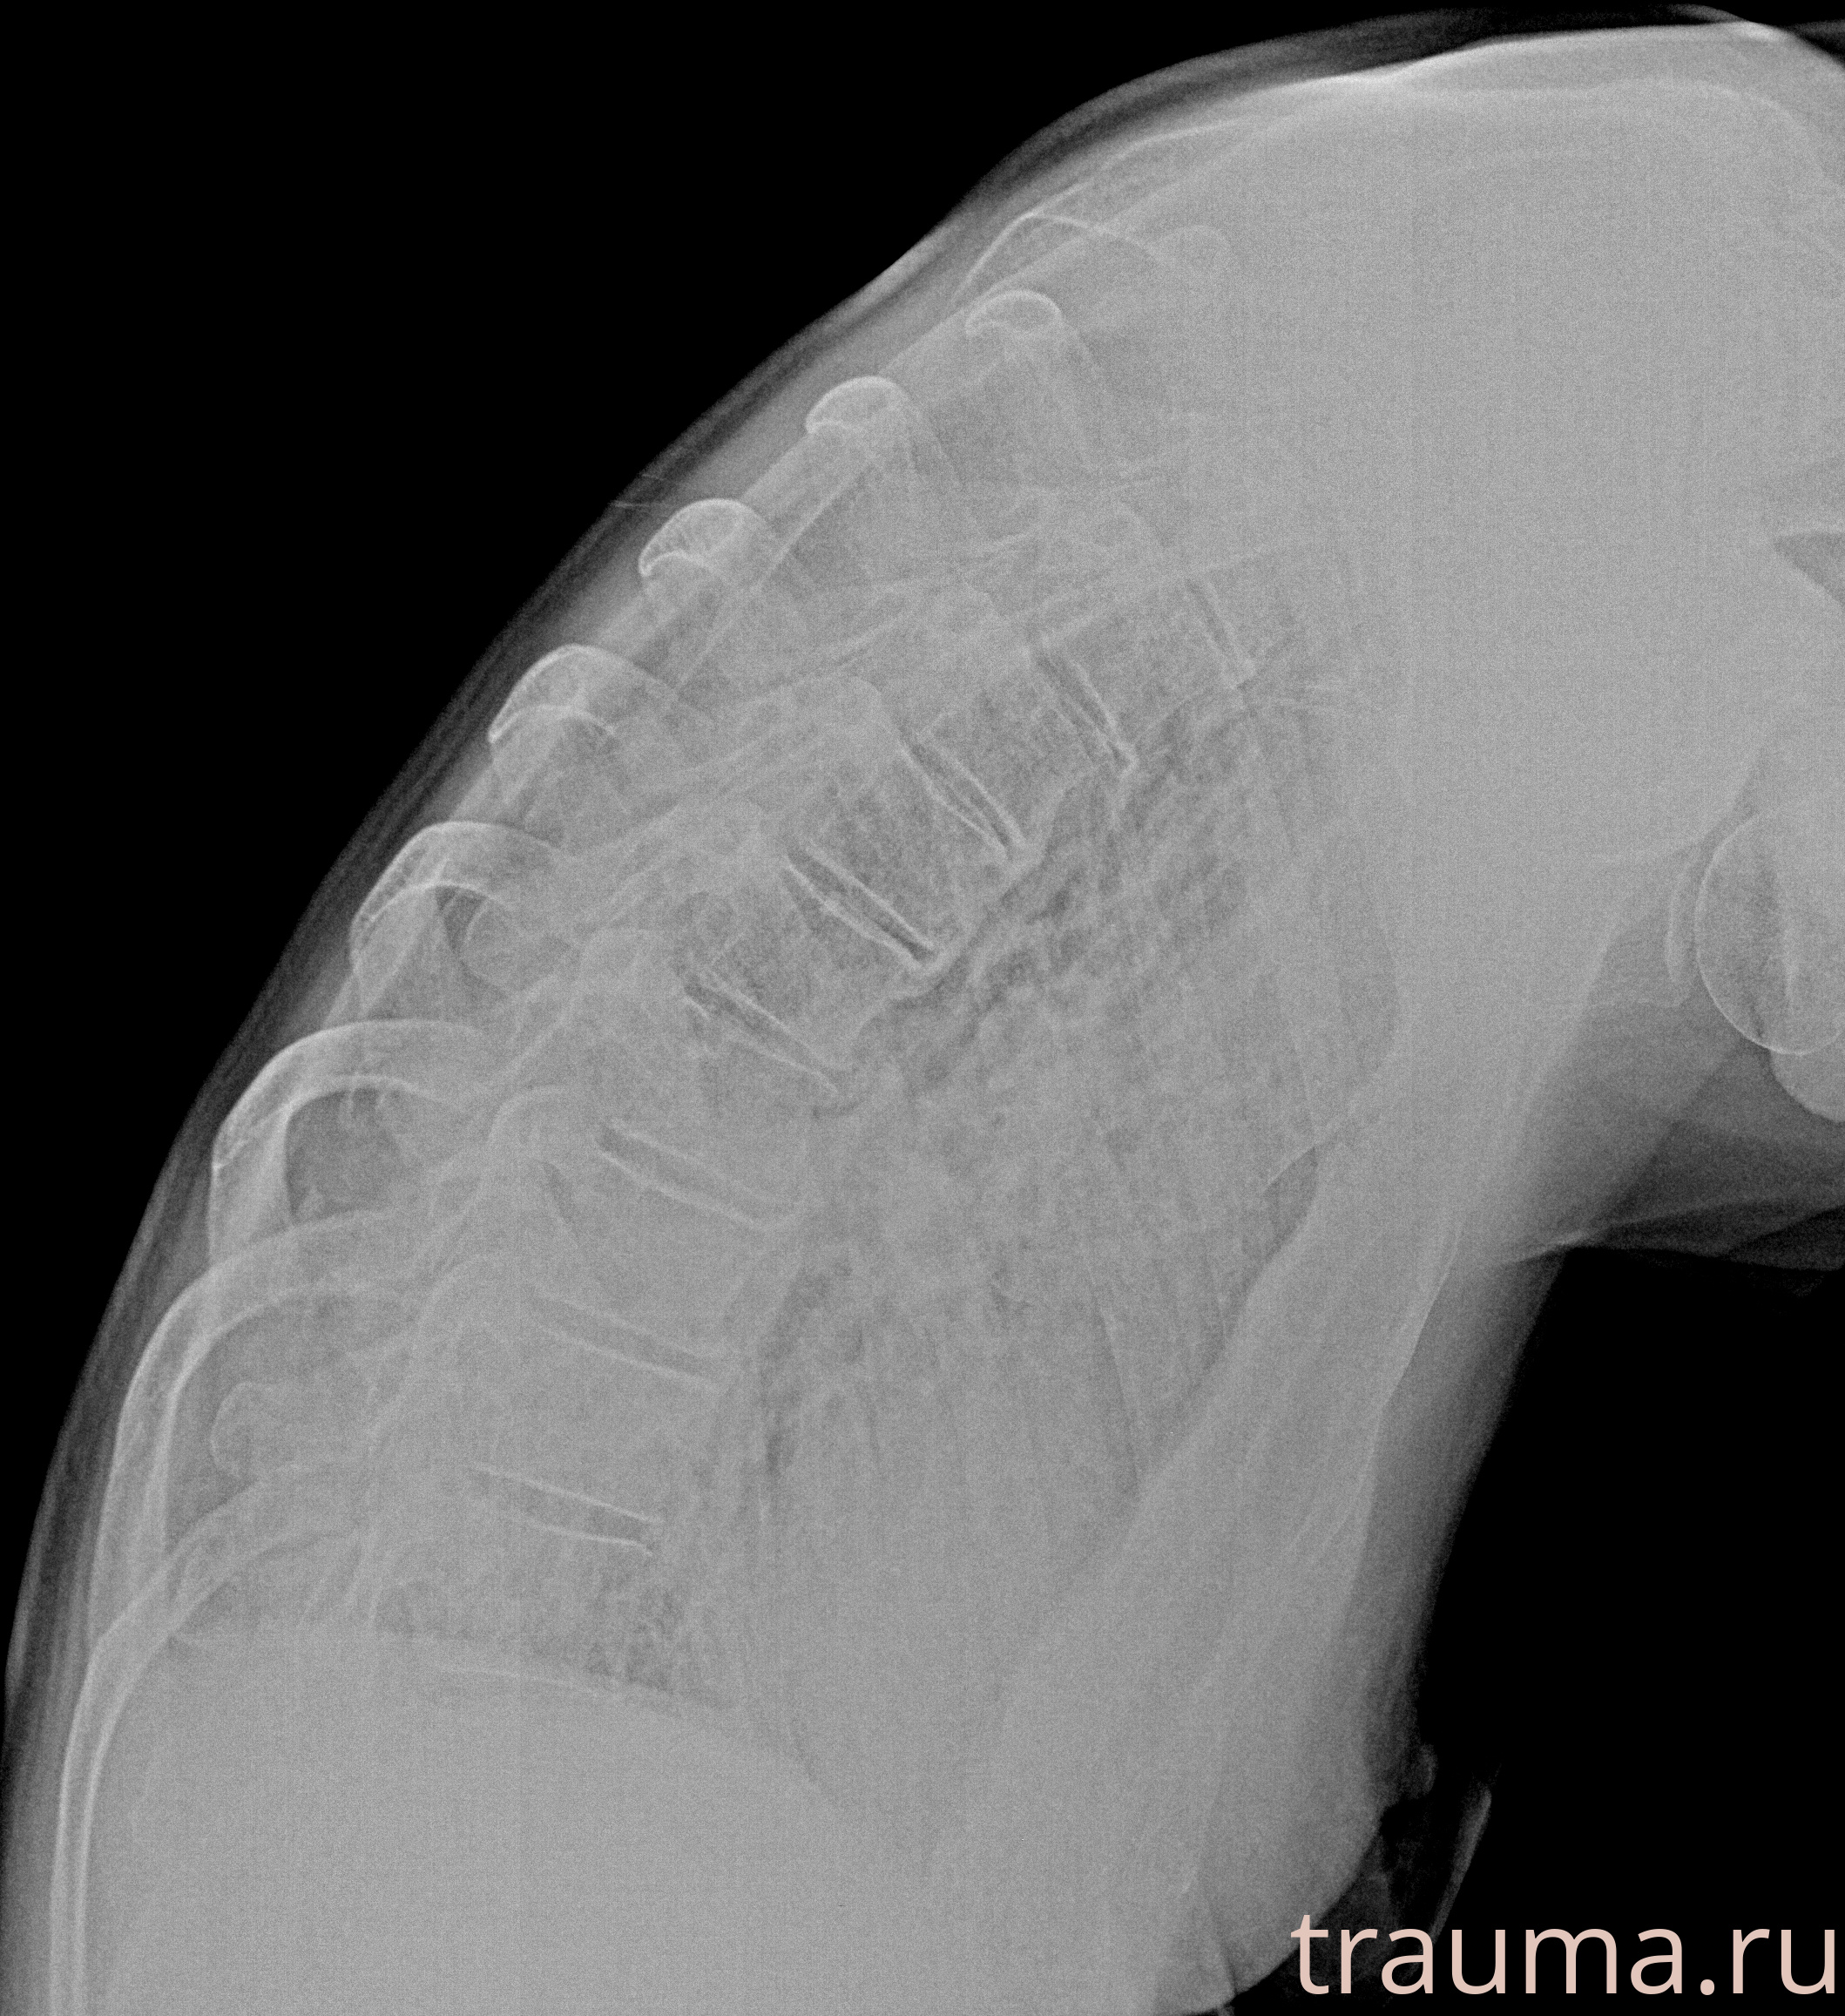

Рентгенограммы

Рентген на дому: по вашему адресу приезжает врач-рентгенолог, травматолог-ортопед с мобильным рентгеновским аппаратом, проводит диагностику травмы или заболевания, делает необходимые рентгенограммы, дает рекомендации по дальнейшему лечению. Получить качественные снимки в домашних условиях возможно благодаря уникальной методике, разработанной МосРентген Центром для института  Склифосовского